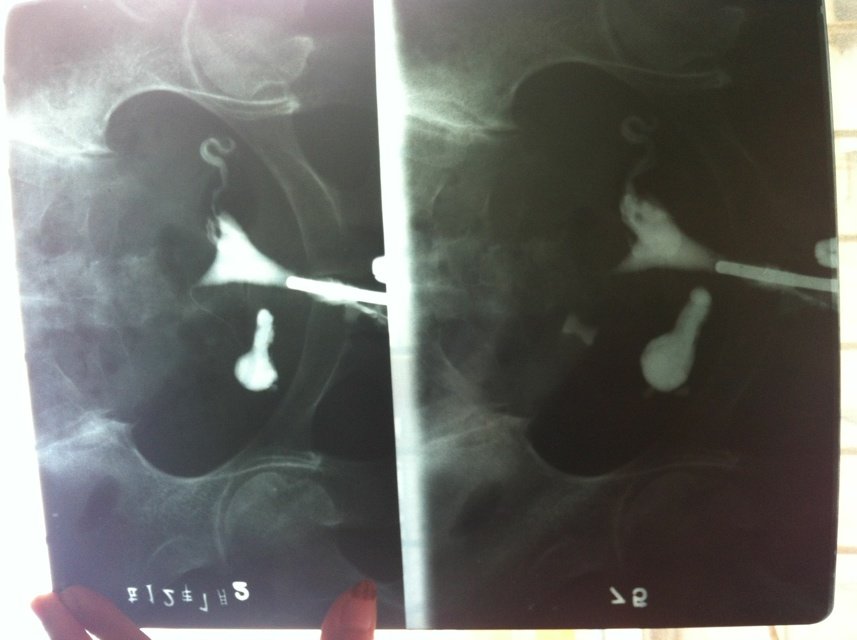

双侧输卵管炎,伞端粘连激液,喝中药灌肠会好吗?希望大家多给点意见,真心不想手术 点击展开 匿名用户 2013-06-02 14:56 为您推荐: 其他回答 可以的,中药稍微好一些 匿名用户 2013-06-02 14:56 相关问题 我想请教一下,输卵管伞端粘连,已经做了三个月的中药灌肠,和理疗还需要再复查吗? 有过宫腔粘连,做过手术,移植失败,宫腔暗区在做灌肠与艾灸,月经来了还可以中药灌肠吗?月经颜色很暗 弟妹有妇科疾病 结婚一年没怀孕 最近在做妇科疾病治疗希望能怀孕 吃了消炎药还有一些中药 还灌肠 热